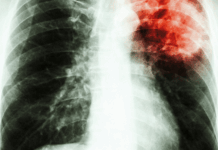

Au-delà du premier mois de vie, les maladies infectieuses, notamment le paludisme, la diarrhée et la pneumonie, demeurent les principales causes de mortalité chez les jeunes enfants. Le paludisme reste la première d’entre elles (il représente 17 % des cas dans cette tranche d’âge), la majorité des décès survenant dans les zones endémiques d’Afrique subsaharienne. Si la mortalité liée à cette maladie avait fortement reculé entre 2000 et 2015, cette baisse s’est nettement essoufflée au cours des dernières années. Les décès demeurent concentrés dans un petit nombre de pays, notamment au Niger, au Nigéria, en République démocratique du Congo et au Tchad – où le paludisme est endémique et où les conflits, les chocs climatiques, les espèces envahissantes de moustiques, la résistance aux médicaments et d’autres menaces biologiques freinent toujours les efforts en matière de prévention et de prise en charge.